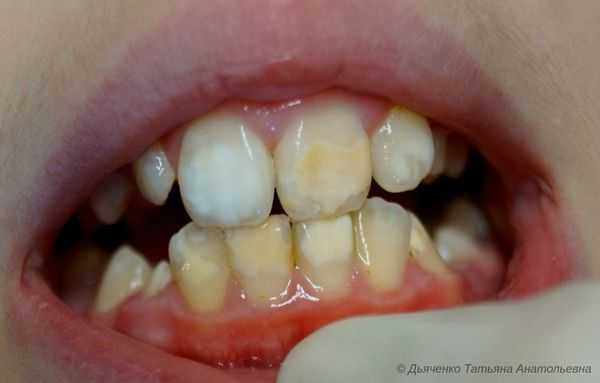

Гипоплазия — это порок развития твёрдых тканей одного или целой группы зубов [13] . Бывает врождённым и приобретённым. Развивается тогда, когда формируются зачатки молочных или постоянных зубов. Не является кариозным поражением.

Сопровождается гипоплазия неоднородным цветом эмали, её истончением и изменением рельефа — углублениями различной формы и величины (от точек до бороздок и ямок). При прорезывании зубы сразу отличаются: на их поверхности присутствуют белые, жёлтые или коричневые пятна.

Симптомы гипоплазии зубов

То, как проявит себя гипоплазия, зависит от тяжести причинного фактора:

- при слабо выраженных нарушениях метаболизма образуются только меловидные (белые) пятна;

- при тяжёлых заболеваниях возникают серьёзные нарушения, вплоть до частичного или полного отсутствия эмали.

По клинической картине выделяют пять форм гипоплазии:

- Пятнистая форма . Сопровождается появлением пятен белого, жёлтого или коричневого цвета. Границы чёткие, поверхность гладкая и блестящая. Форма, размер и расположение пятен чаще симметрично.